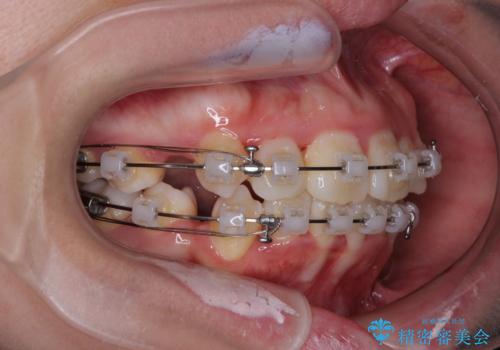

- クリアブラケット

- 飛び出した上顎の前歯と八重歯を気にして来院された患者様です。

口元を積極的に引っ込めるために、上下左右の小臼歯計4本を抜歯することとしました。

舌の突出癖が強いため、しっかりと口元を引っ込めるため、舌のトレーニングをしっかりと行いながら矯正治療を行うこととしました。